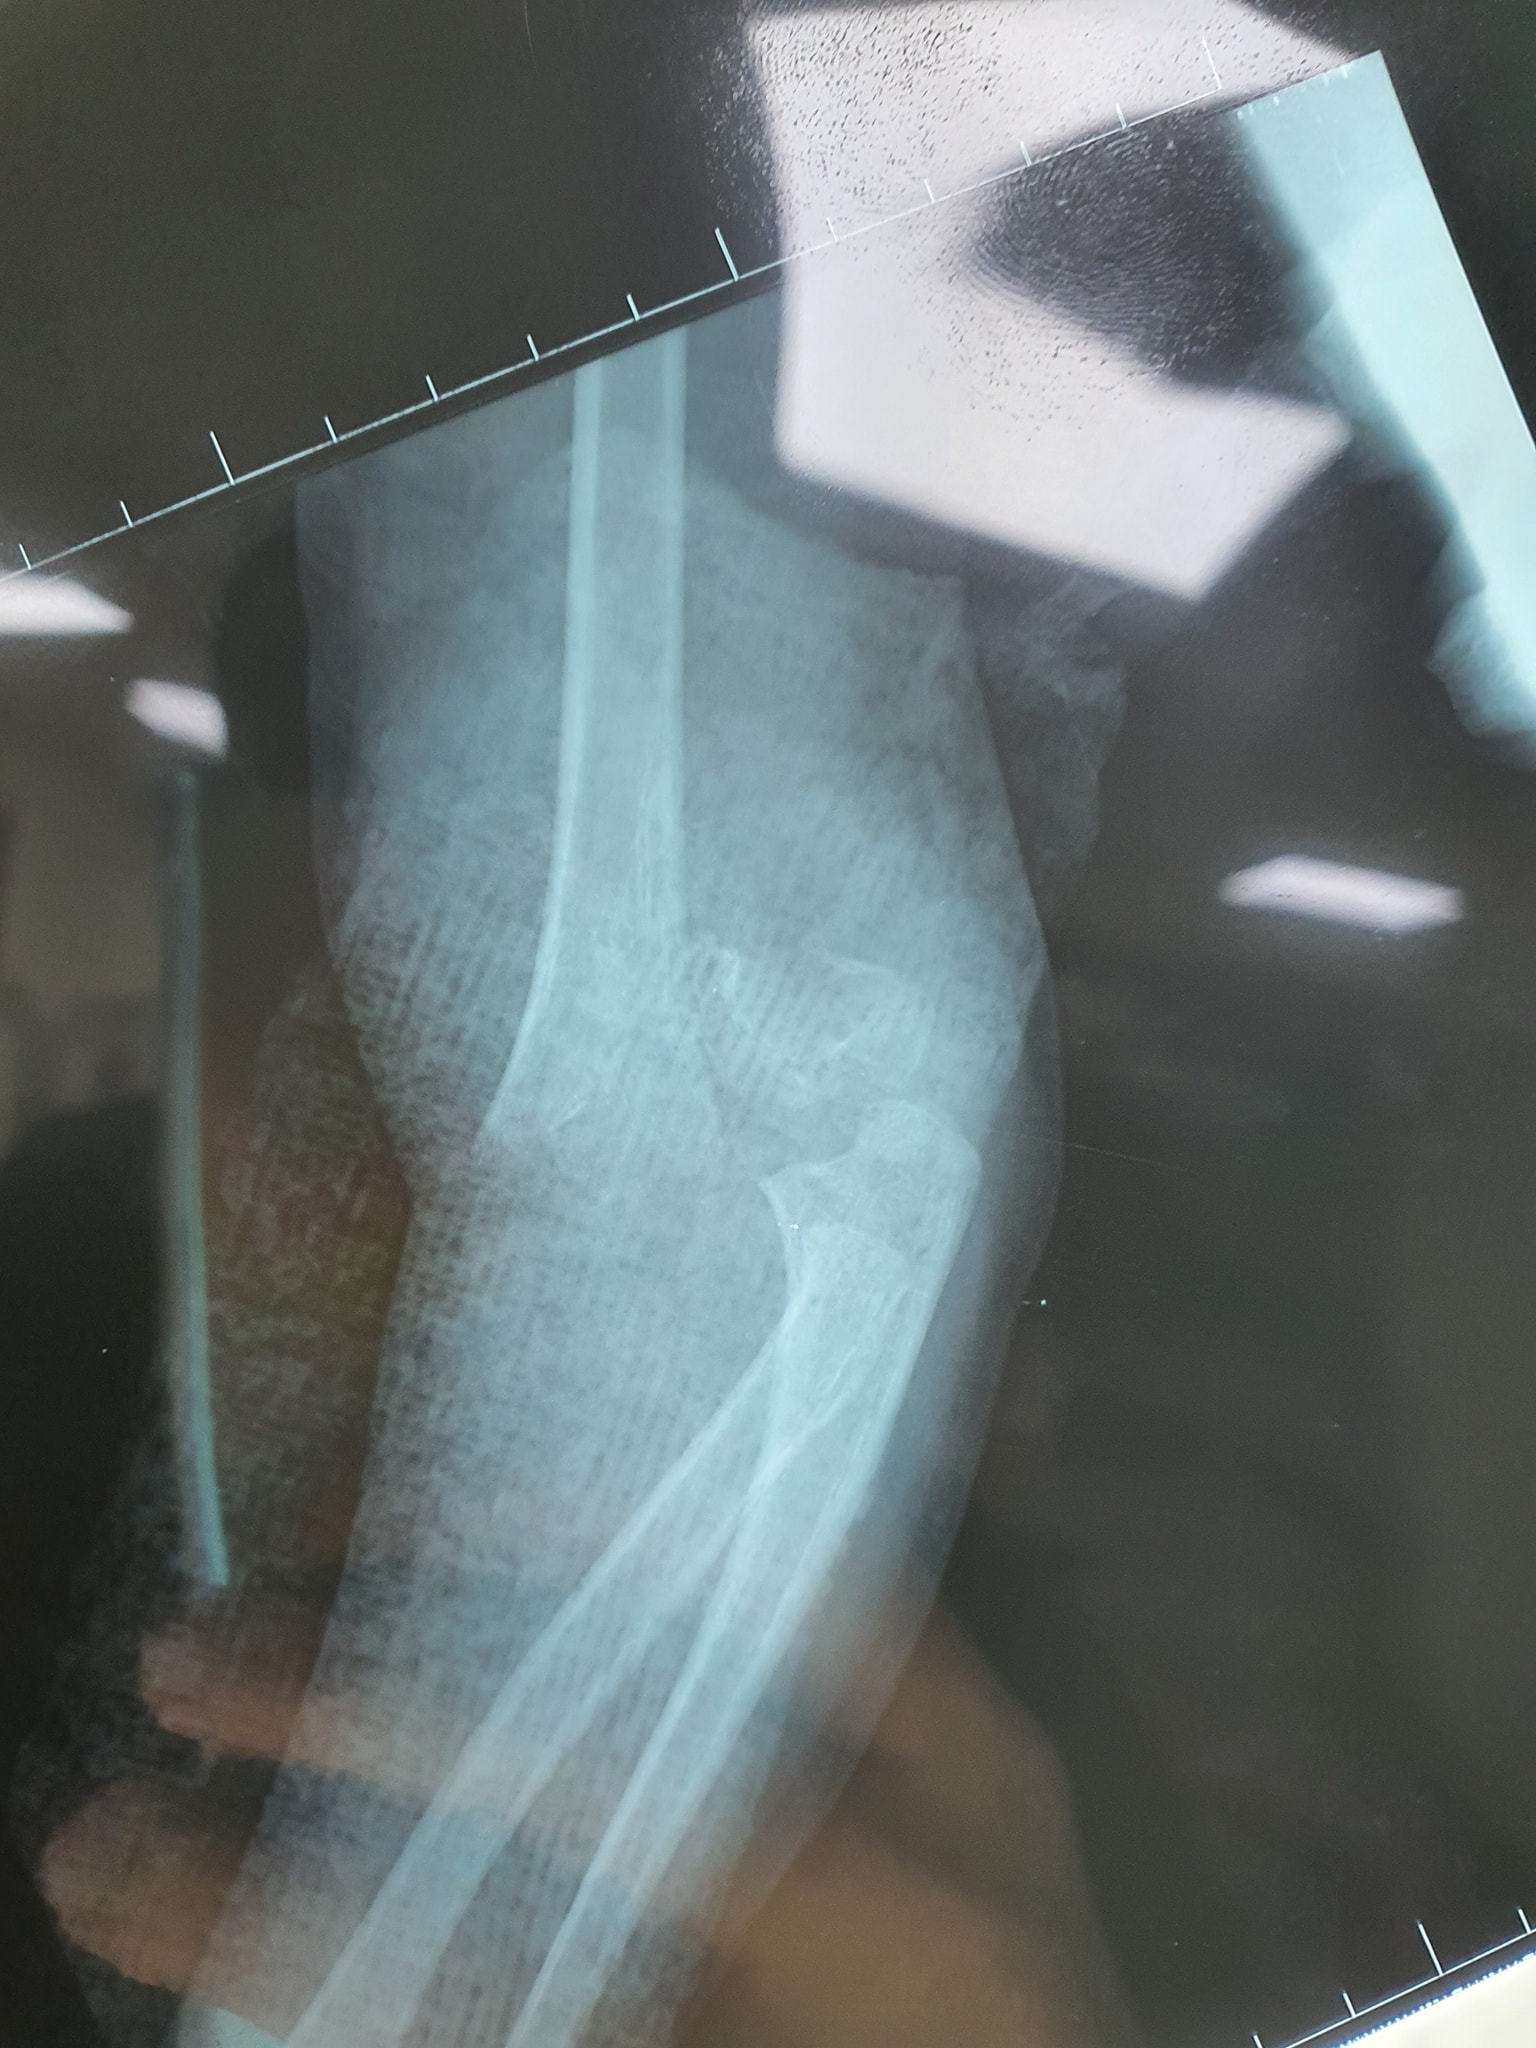

كافة انواع الكسور وعلاجها